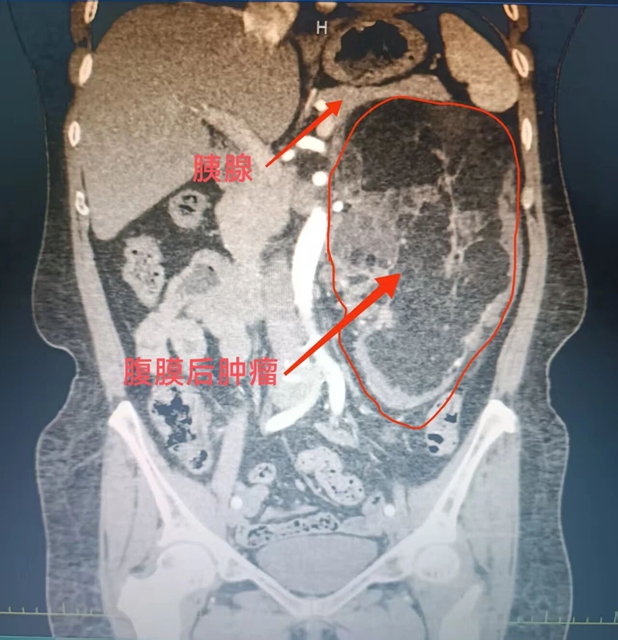

结束一天忙碌,约上三五好友撸串、喝夜啤酒,是不少人放松身心的选择。但这份惬意背后,可能藏着意想不到的健康风险。近期,西南医科大学附属中医医院就收治了一位因撸串饮酒后,半夜口吐大量鲜血的患者。  患者张先生回忆,事发前一晚,他为招待外省朋友...